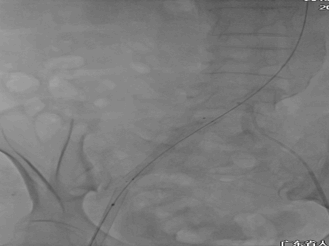

更换19F大鞘完成TAVR

双侧造影证实真腔DSA

植入巴德ZVL10060支架

复查造影